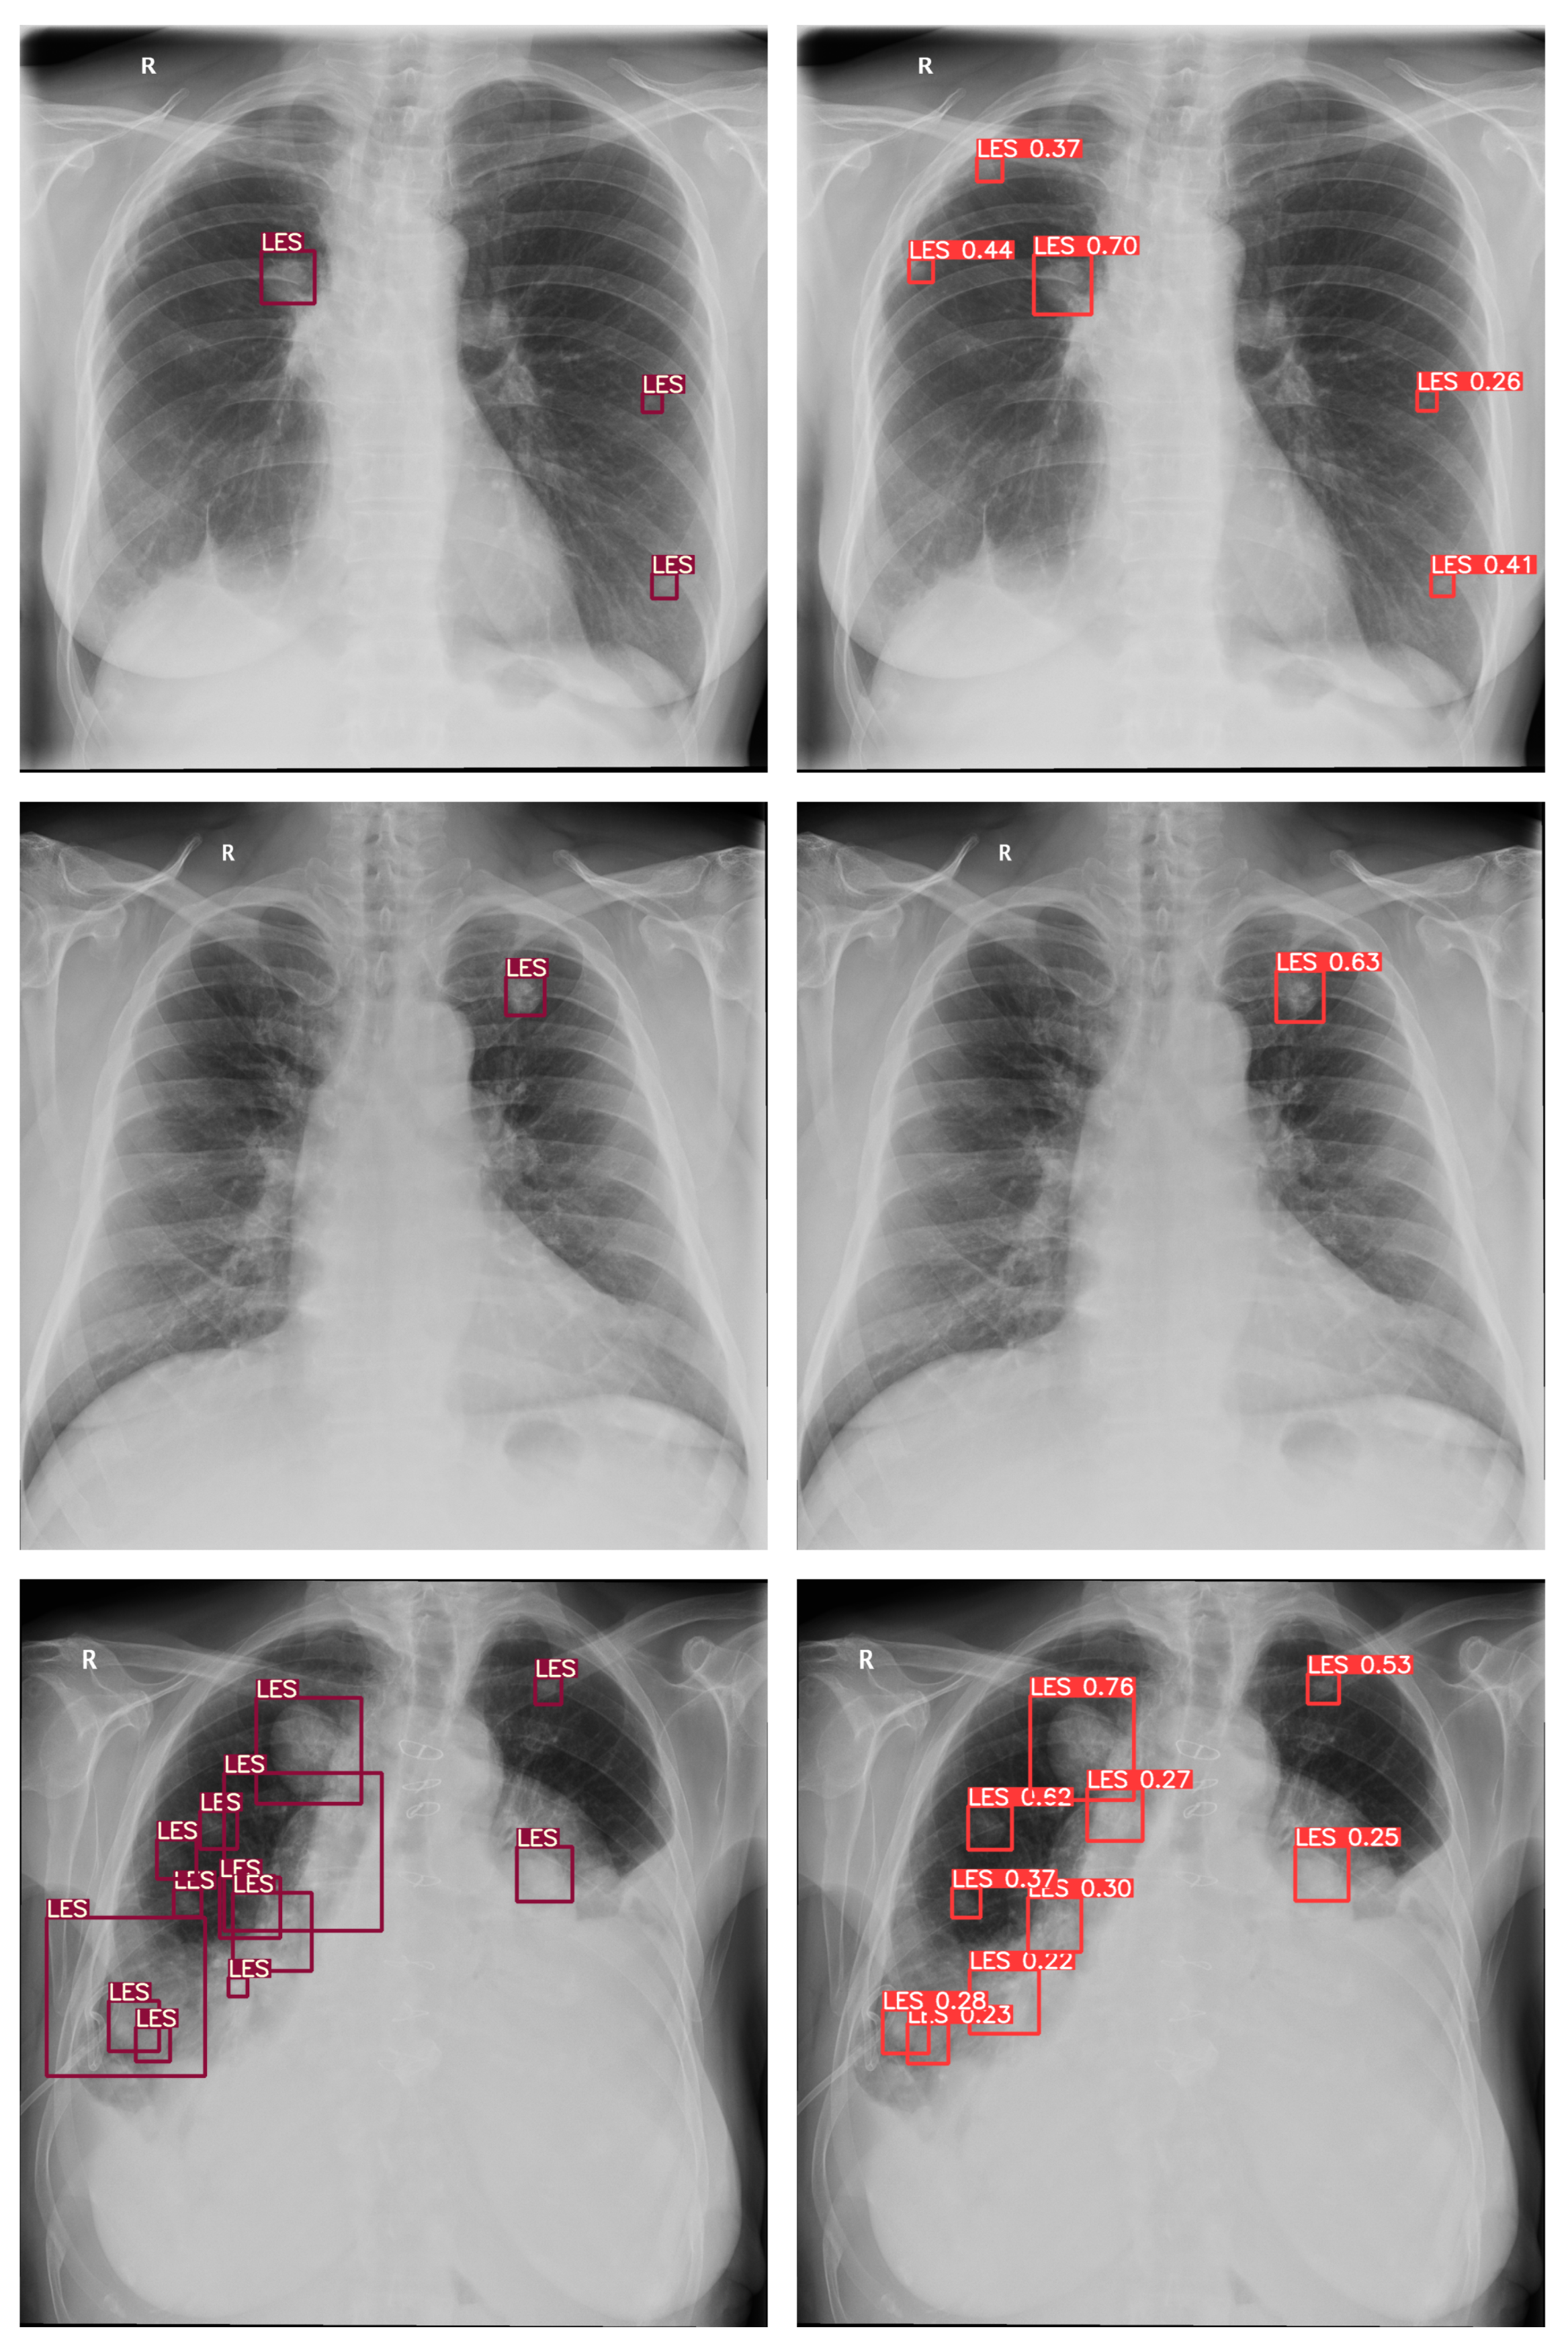

3. Materials and Methods

3.1. Software